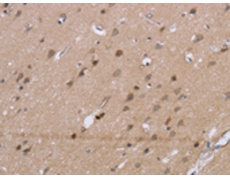

IHC positive control: |

Human brain and Human thyroid cancer |